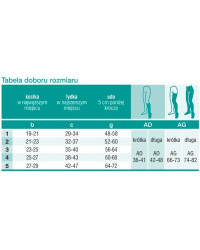

Dobór rozmiaru

Warunkiem właściwego działania produktów kompresujących, jest dobór odpowiedniego rozmiaru.

Aby dobrać odpowiedni rozmiar należy zmierzyć obwód i długość nóg w odpowiednich miejscach, wskazanych w tabeli.

Pomiary punktów:

b - kostka w najwęższym miejscu

c - łydka w najszerszym miejscu

Rozmiary:

1 - S, 2 - M, 3 - L, 4 - XL, 5 - XXL

Długość nóg:

➡️ AD - podkolanówki

➡️ AG - pończochy i rajstopy

➡️ Podkolanówki długość krótka: 36 - 41 cm

➡️ Podkolanówki długość długa: 42 - 48 cm